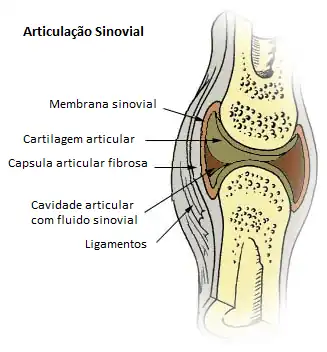

Articulações

As articulações são estruturas formadas por tecido conjuntivo que unem os ossos entre si, formando o esqueleto. Elas podem ser classificadas em diartroses, que permitem grande movimento dos ossos (vide imagem), e sinartroses, nas quais não ocorrem movimentos ou estes são muito limitados.

Nas diartroses existe uma cápsula que liga as extremidades ósseas, delimitando uma cavidade fechada, a cavidade articular. Ela contém um líquido incolor, transparente e viscoso, o líquido sinovial, com alta concentração de ácido hialurônico, molécula com efeito lubrificante que facilita o movimento articular.

A resiliência da cartilagem é um eficiente amortecedor das pressões mecânicas intermitentes que são exercidas sobre a cartilagem articular. Mecanismos semelhantes ocorrem nos discos intervertebrais.